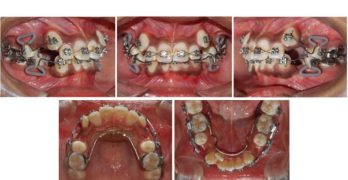

Para comenzar la semana traemos un artículo llamado Asymmetric mandibular arch distalization with third-molar … [Leer más...] acerca de Distalización asimétrica con extracción de terceros molares para la corrección no quirúrgica de la mordida abierta esqueletal clase III y desviación mandibular

Distalización asimétrica con extracción de terceros molares para la corrección no quirúrgica de la mordida abierta esqueletal clase III y desviación mandibular